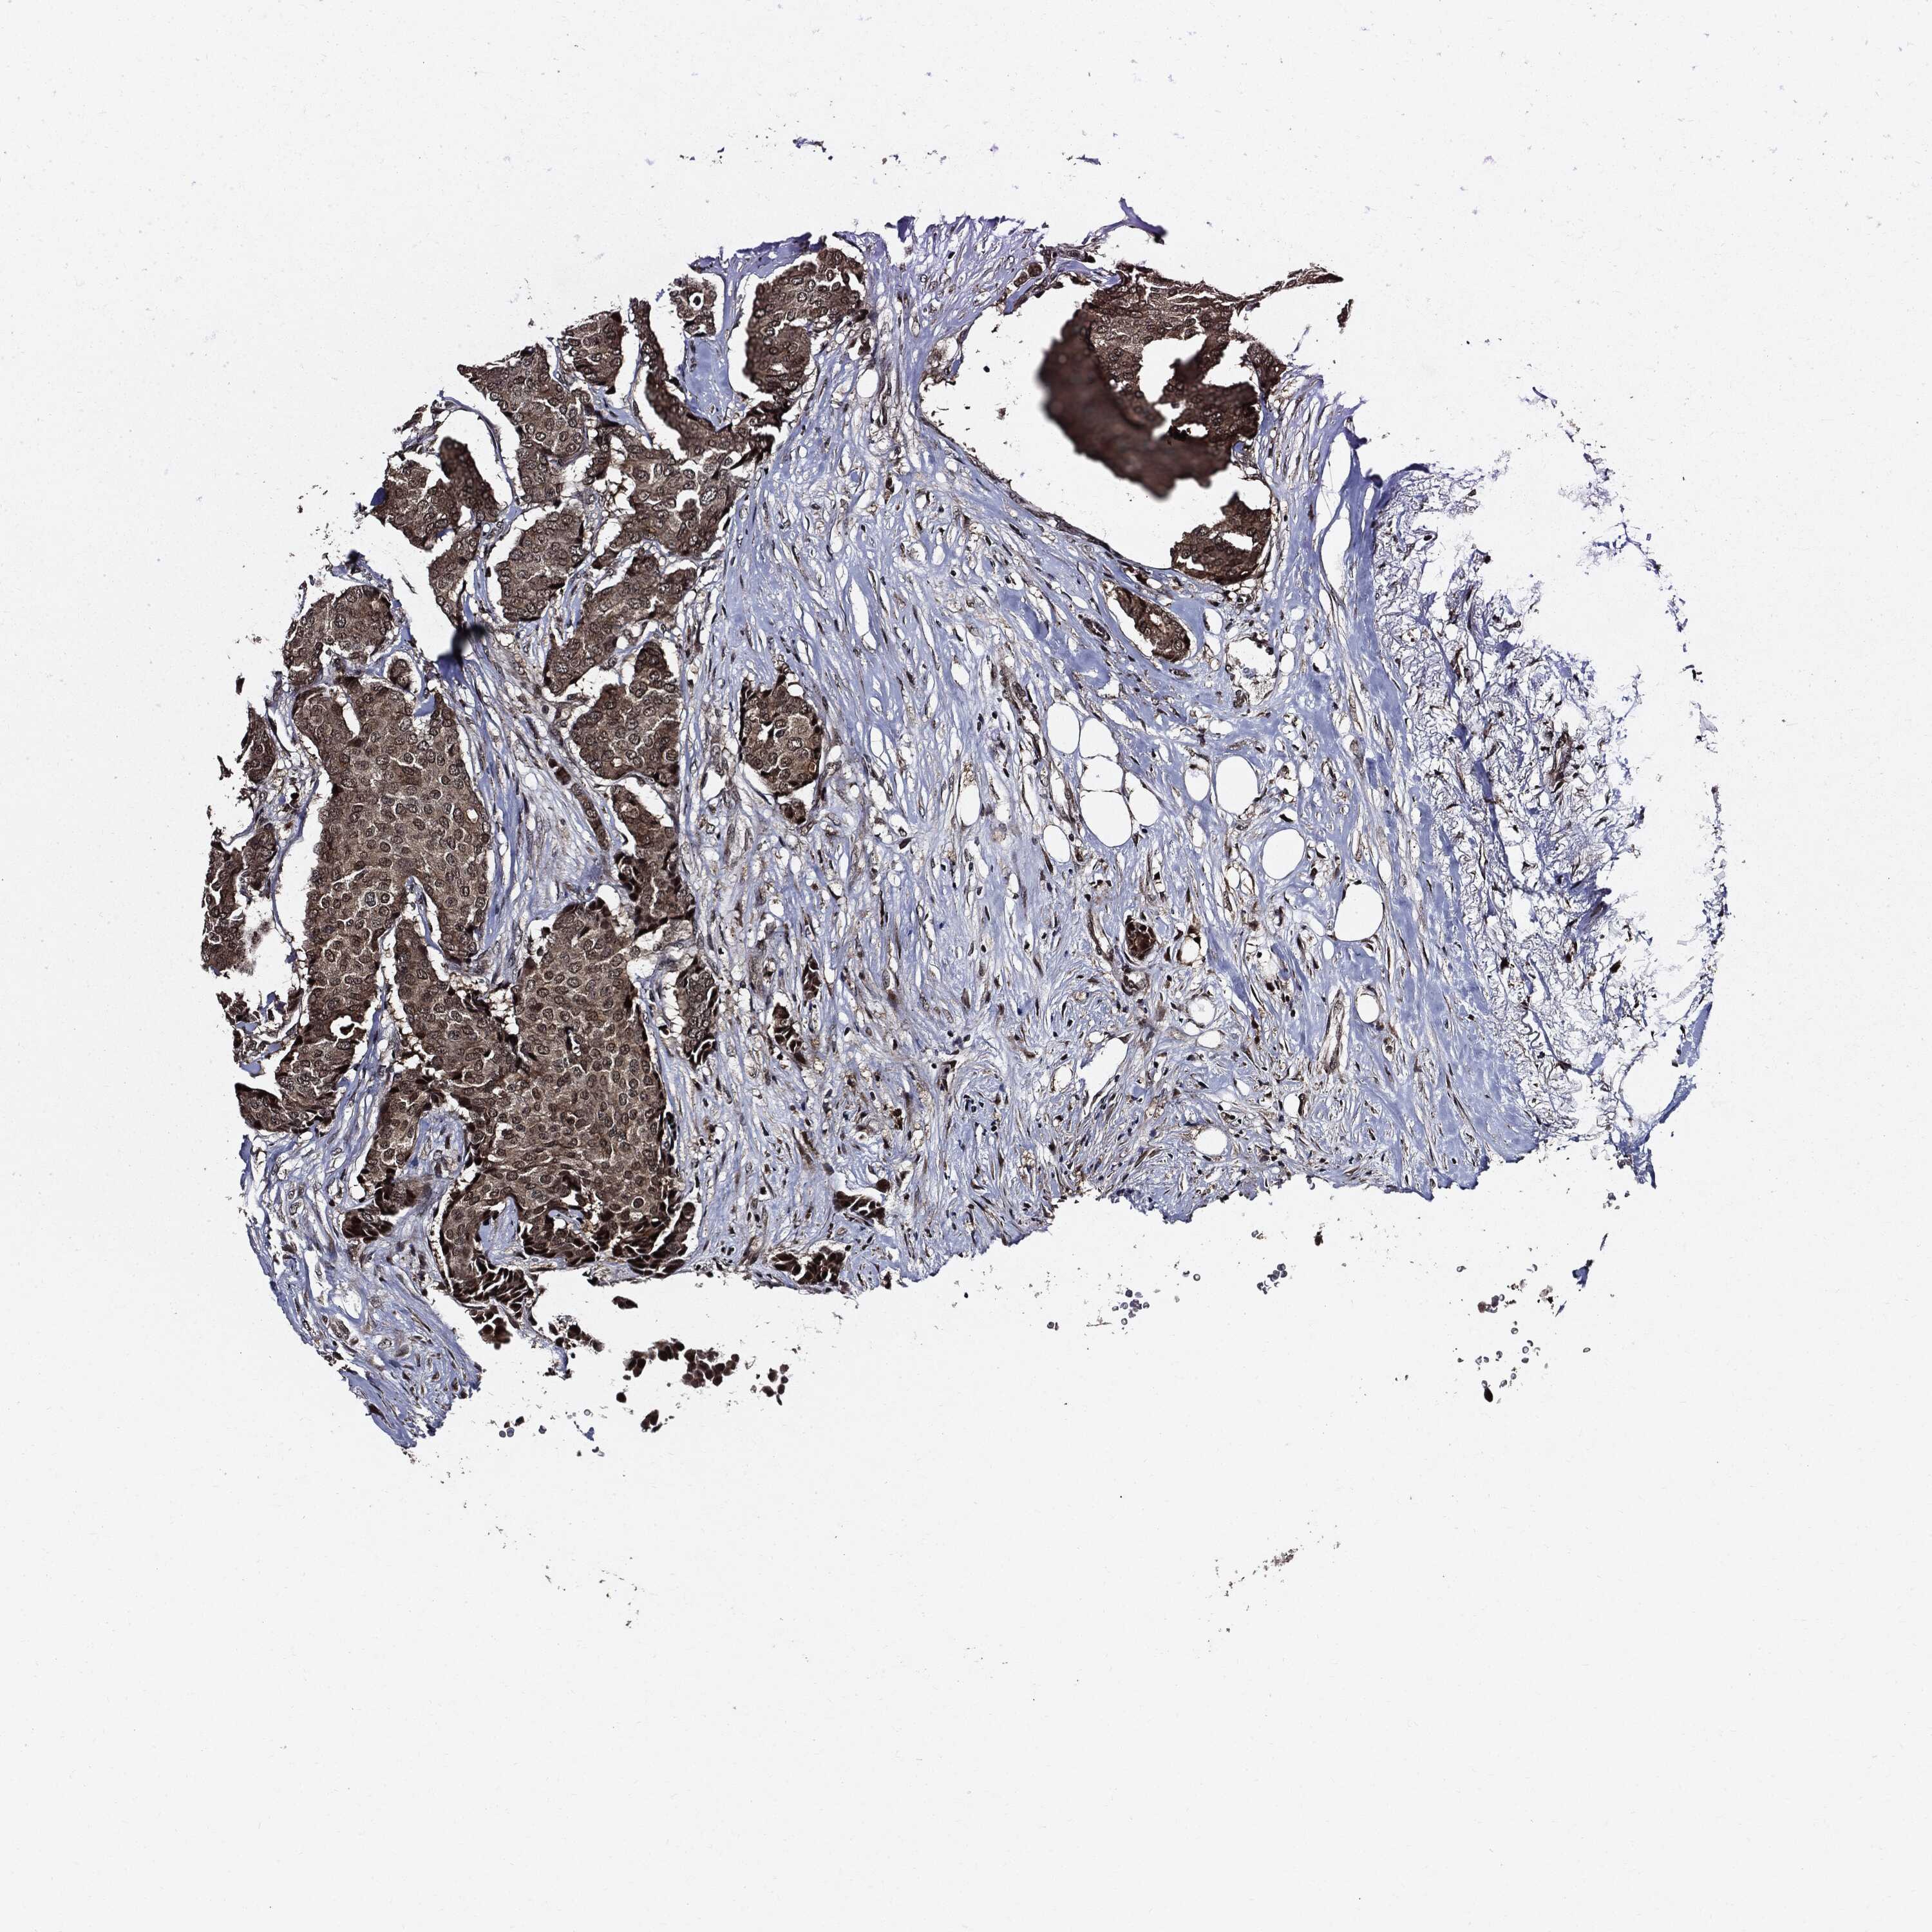

BRCA TCGA BRCA VALIDATION PROTEIN EXPRESSION

ANTIBODIES

AND

VALIDATION